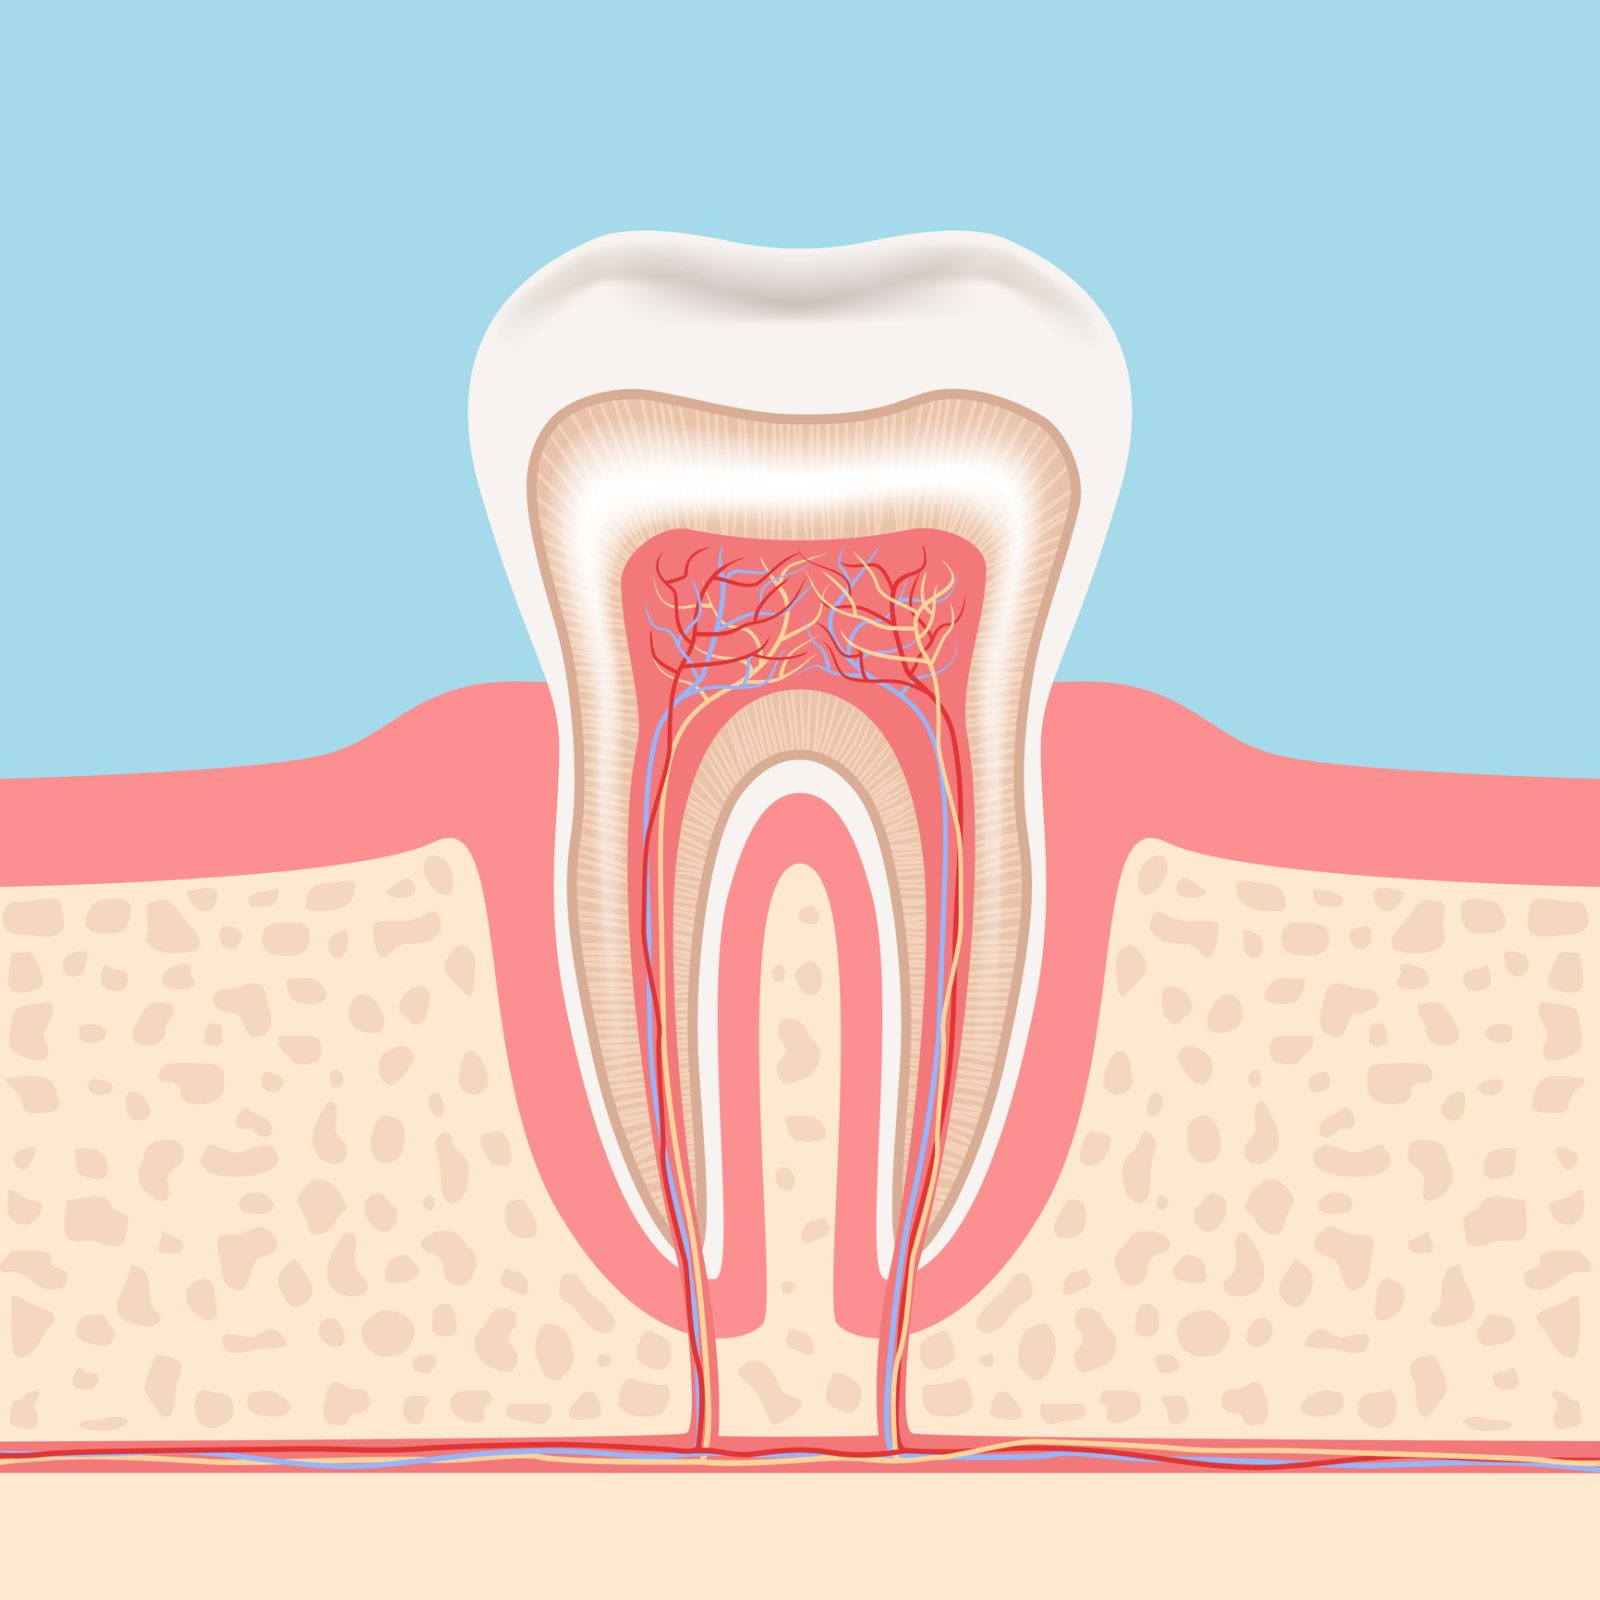

歯の神経には、歯に栄養を与える役割があります。神経を失った歯は栄養を取り入れられなくなり、時間と共に弱くなっていきます。

まず、実際に「根管」の画像をご覧ください。歯の内部にある黒い筋が根管で、その形状は非常に複雑です。特に狭い部分では直径が1mmにも満たないことがあります。

このような細い根管から、細菌に感染した組織をきれいに取り除く作業は、非常に難しいものとなります。